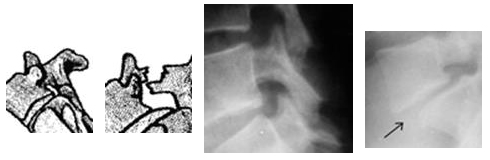

La palabra “espondiolistesis” deriva de dos términos: “espóndilo”, que significa columna vertebral, y “listesis”, que significa desplazamiento. Por lo tanto, la espondiolistesis es el desplazamiento hacia delante de una vértebra (es decir, uno de los 33 huesos de la columna vertebral) respecto de otra. La espondiolistesis suele ocurrir en la base de la columna, en la zona lumbar.

La espondiolistesis puede describirse de acuerdo con su grado de gravedad. Una descripción utilizada frecuentemente clasifica la espondiolistesis en grados, siendo el grado 1 el menos avanzado y el grado 5, el más avanzado. La espondiolistesis se clasifica en grados midiendo cuánto se ha desplazado la vértebra hacia delante sobre la vértebra subyacente.

- Grado 1: 25% de la vértebra se ha desplazado hacia adelante

- Grado 2: 50%

- Grado 3: 75%

- Grado 4: 100%

- Grado 5: La vértebra se ha desplazado totalmente (es decir, espondiloptosis)